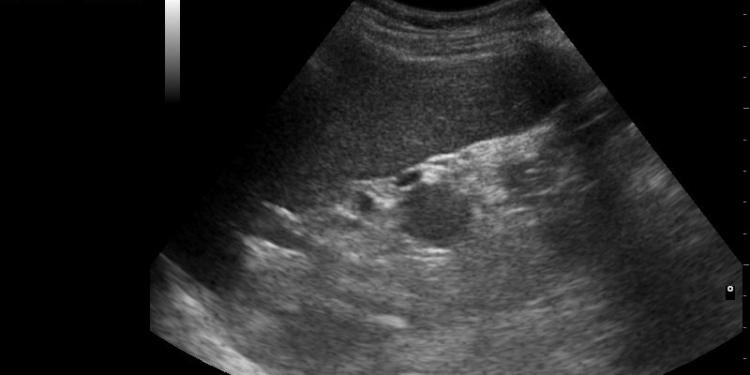

Republican Gov. Doug Burgum signed a similar bill into law in April 2023 after the state Senate passed the legislation in a 37-9 vote, according to Live Action. The law requires schools to include a “human growth and development discussion” that utilizes an ultrasound video as well as a “computer-generated rendering or animation” that shows human development at all stages.